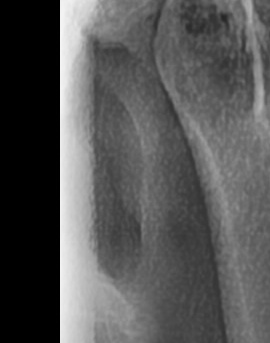

가장 주의해야 하는 문제 중에 치주염이 진행되면 어금니 뒤쪽뿐만 아니라 전체적인 잇몸이 약해질 수 있어요. 치주염은 치아를 둘러싸고 있는 조직이 손상되는 질환인데 특히 잇몸이 자주 붓거나 피가 나는 경우에는 치주염이 진행되고 있는 신호일 수 있기 때문에 단순한 잇몸 붓기로 넘기지 않는 것이 좋으며 치료를 받지 않으면 결국 치아를 지탱하는 뼈가 약해지고, 심한 경우에는 치아가 흔들리거나 빠질 수도 있었어요.

결론적으로는 통증이 심하거나 염증이 오래 지속되는 경우에는 치과를 방문해서 정확한 진단을 받는 것이 중요한데 단순한 잇몸 염증이라면 치석 제거와 항생제 치료로 호전될 수 있지만, 치주염이 진행된 경우라면 보다 적극적인 치료가 필요할 수 있어요. 만약 사랑니로 인해 잇몸이 자꾸 붓는다면 사랑니 발치를 고려해야 하겠고 사랑니가 완전히 매복되어 있다면 수술적인 방법으로 제거해야 할 수도 있어요. 특히 반복적으로 붓는다면 사랑니 검사를 받아보거나, 치과에서 정밀 검진을 통해 치주 상태를 확인하는 것이 필요하다는 점에서 어금니 근처의 잇몸이 반복적으로 불편하다면 꼭 치과를 찾아보시길 바라고 있어요